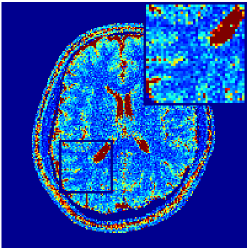

Two sets of experiments were conducted here: first, we used the 2D and 3D acquisition sequences for scanning a healthy volunteer’s brain (real-world acquisitions). Figures 6 and 7 display the parametric maps reconstructed from 2D spiral and radial readouts. We computed the T1, T2 and proton density (PD) maps using baseline reconstruction algorithms ZF, VS, LR, FLOR, AIR-MRF and our proposed LRTV. While baselines use DM either for quantitative inference or also during reconstruction (i.e. AIR-MRF), we further compare the DM-free LRTV’s performance when cascaded to DM, KM and MRFResnet for quantitative inference. For the 3D spiral acquisitions we compared LRTV and its closest competitor VS in Figure 8. Outcomes from other tested algorithm are displayed in the supplementary materials (Figure S5). Since FLOR does not use dimensionality-reduction, our system ran out of memory during 3D reconstruction; hence results are not reported in this case.

VI-E1 Discussion

The LRTV-DM and LRTV-MRFResnet perform on par, and both outperform all tested baselines for reconstructing T1, T2 and PD maps in all acquisition schemes. This can be observed both visually in Figures 6, 7, 8, S2 and S3, and quantitatively in Table IV across all tested metrics. Other baselines were unable to successfully remove the under-sampling artefacts in TSMIs, and these errors propagated to the parameter inference phase and resulted in inaccurate maps. Temporal-only priors incorporated within LR are shown insufficient to regularise the inverse problem and LR sometimes (e.g. 2D spiral acquisitions) can admit solutions with even stronger artefacts than the model-free ZF baseline. This issue was previously studied for other non-Cartesian MRF readouts that similar to our spiral/radial trajectories, miss to sample the corners of the k-space in all timeframes (see section 2.2.2 and figure 2 in [19]). In the absence of reference for the k-space corners information, the LR iterations despite minimising the objective can converge to solutions with high-frequency artefacts, as visible in the computed maps. This highlights the need for adding an appropriate spatial-domain regularisation. FLOR reduces the LR’s artefacts but this improvement is limited because the suggested nuclear norm penalty does not incorporate an explicit spatial regularisation. Further for reducing artefacts, FLOR can introduce an undesirable bias in the computed T1/T2 maps e.g. see error maps in Figures S2 and S3. The non model-based VS baseline incorporates spatial regularisation and results in spatially smoother maps than ZF and LR, but it is unable to output artefact-free images. Further and consistent with our in-vitro experiment, we observe that VS overestimates the T2 values (e.g. in White and Grey matter regions) in tested 2D acquisitions i.e. the spatial regularisation trades off agains the quantification accuracy. The model-based AIR-MRF adds spatial regularisation through 2D/3D low-pass Gaussian filters however this trades off the sharpness of the computed maps and can increase the errors at the tissue boundaries (we searched Gaussian spreads that keep the blurs and high-frequency artefacts minimal). For our acquisition readouts, Gaussian filters performed better than disk filters of [19] for avoiding strong Gibbs artefacts. On the other hand, the spatiotemporally regularised LRTV greatly improves the TSMI reconstructions i.e. 4 dB enhancement compared to the closest competitor baseline (Table IV). This enables computing accurate and aliased-free multi-parametric inference using DM or the DM-free learning-based alternative MRFResnet as visible in Figures 6, 7, 8, S2 and S3. MRResnet and DM score competitive quantitative inference results i.e. T1 and T2 MAPE less than 5% and 9%, respectively (Table IV). KM also outputs comparably accurate T1 maps, however this shallow learning model despite having a model size larger than MRFResnet, is unable to learn accurate T2/PD quantification and it results in poor estimated maps, consistent with our observations in section VI-C.